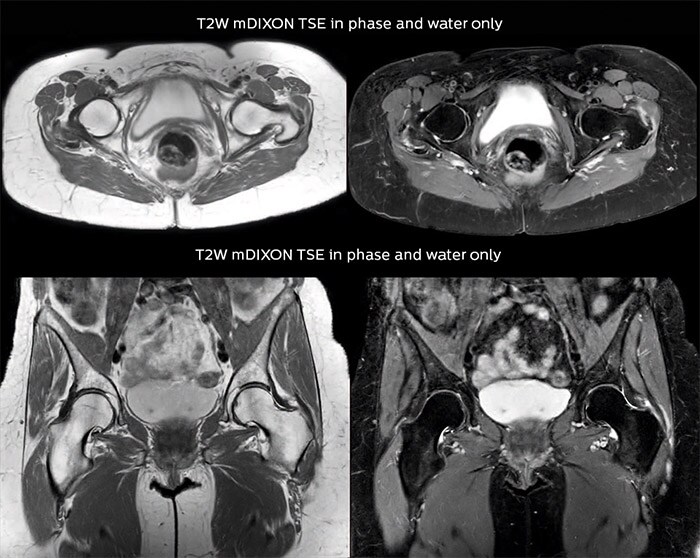

“For bone assessment near joints, mDIXON TSE provides the visualization and multiple contrasts to describe abnormalities within a limited number of acquisitions. Bone marrow signal abnormalities are common MRI findings that can represent various underlying causes, from normal variance to malignancy. So, it is important for us to notice and characterize these findings. With different contrasts, both with and without fat signal as mDIXON TSE efficiently provides, we can make a confident diagnosis.” “Other examples in bone are the signal description of a necrotic fragment in osteonecrosis, the signal description of tumoral matrix that has different components (necrosis, hemorrhage, cartilage, bone formation). These are all possible thanks to in-phase and water images from a single mDIXON acquisition.”

Fat suppressed images appear homogeneous over the entire image, even with large coverage at 3.0T – for instance in scapular or hip girdles – or in the bearing areas or around metal prostheses, where fat suppression is often deficient with STIR or spectral fat suppression, causing diagnostic difficulties. If a diagnostic image is right the first time, we don’t need to repeat or add a sequence.” “mDIXON TSE sequences allow simultaneous characterization of morphological changes from the in-phase T2-weighted images and visualization of edematous changes, thanks to the water T2-weighted images from the same acquisition. Anatomical and morphological considerations could be a partial or complete ligament tear, a bony avulsion or hematoma.” “For soft tissue assessment mDIXON brings similar benefits. For example in one T2-weighted mDIXON TSE acquisition, having the multiple contrasts helps us assess abnormalities in peripheral nerves fascicles, which may be due to anatomical or inflammatory changes..”